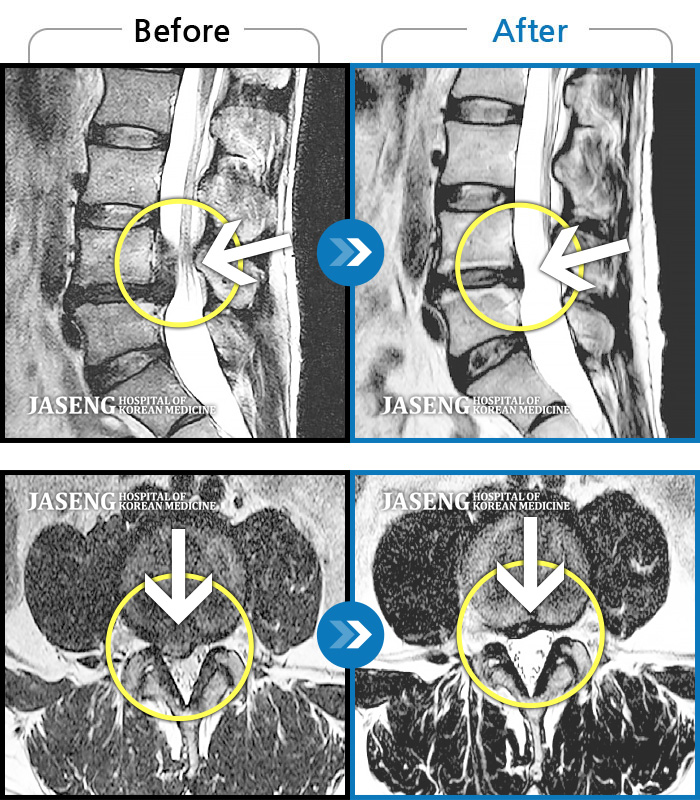

MRI ũ ʸ Ȯϼ.

[ؿ] 24.10.10~25.04.23